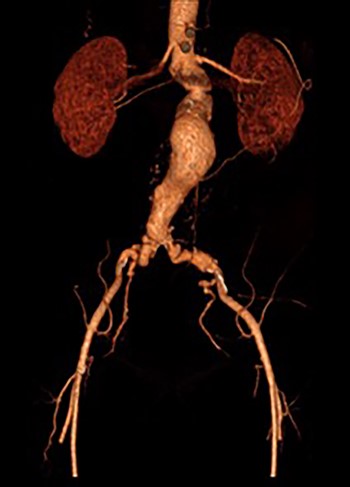

3D reconstruction CT scan, at 6-week interval from index procedure.

The patient was transferred to the high-dependency unit for observation during the thrombolysis. After 4-h, the patient was taken back to Interventional Radiology department for a check angiogram (Fig. 3). This demonstrated a fully re-canalized aorto-iliac system with no distal thrombotic or embolic complications. The thrombolysis infusion was stopped at this stage. In the post-operative period, anticoagulation has been continued with Apixaban. A CT scan 6 weeks post-procedure has confirmed ongoing patency of the endograft with no visible thrombus (Fig. 4).